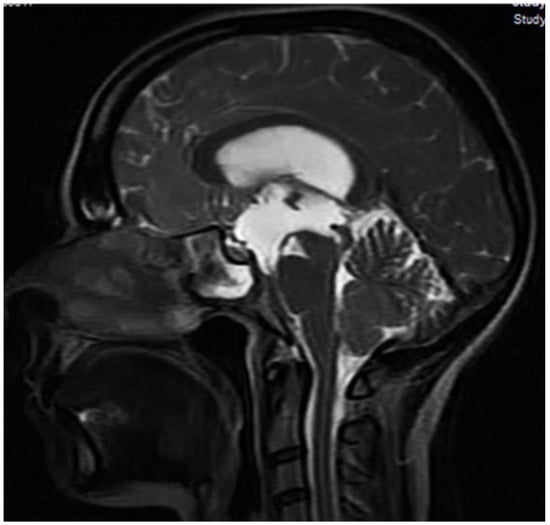

2. Case Presentation

Implantation Techniques and Devices